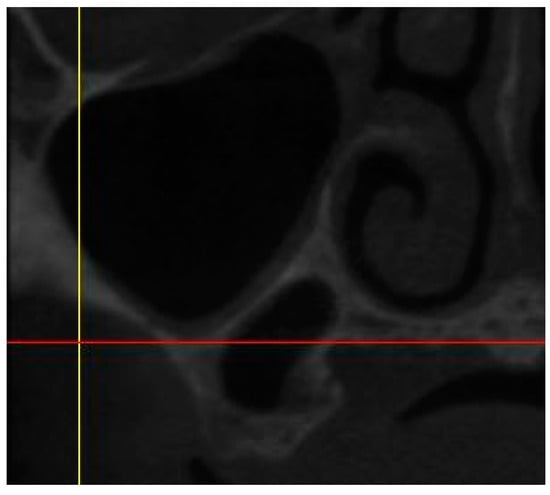

• The presence of sinus septum, membrane thickening, and/or pathology (Figure 3).

They were noted as yes/no.

Figure 3. CBCT image showing the presence of sinus septum.